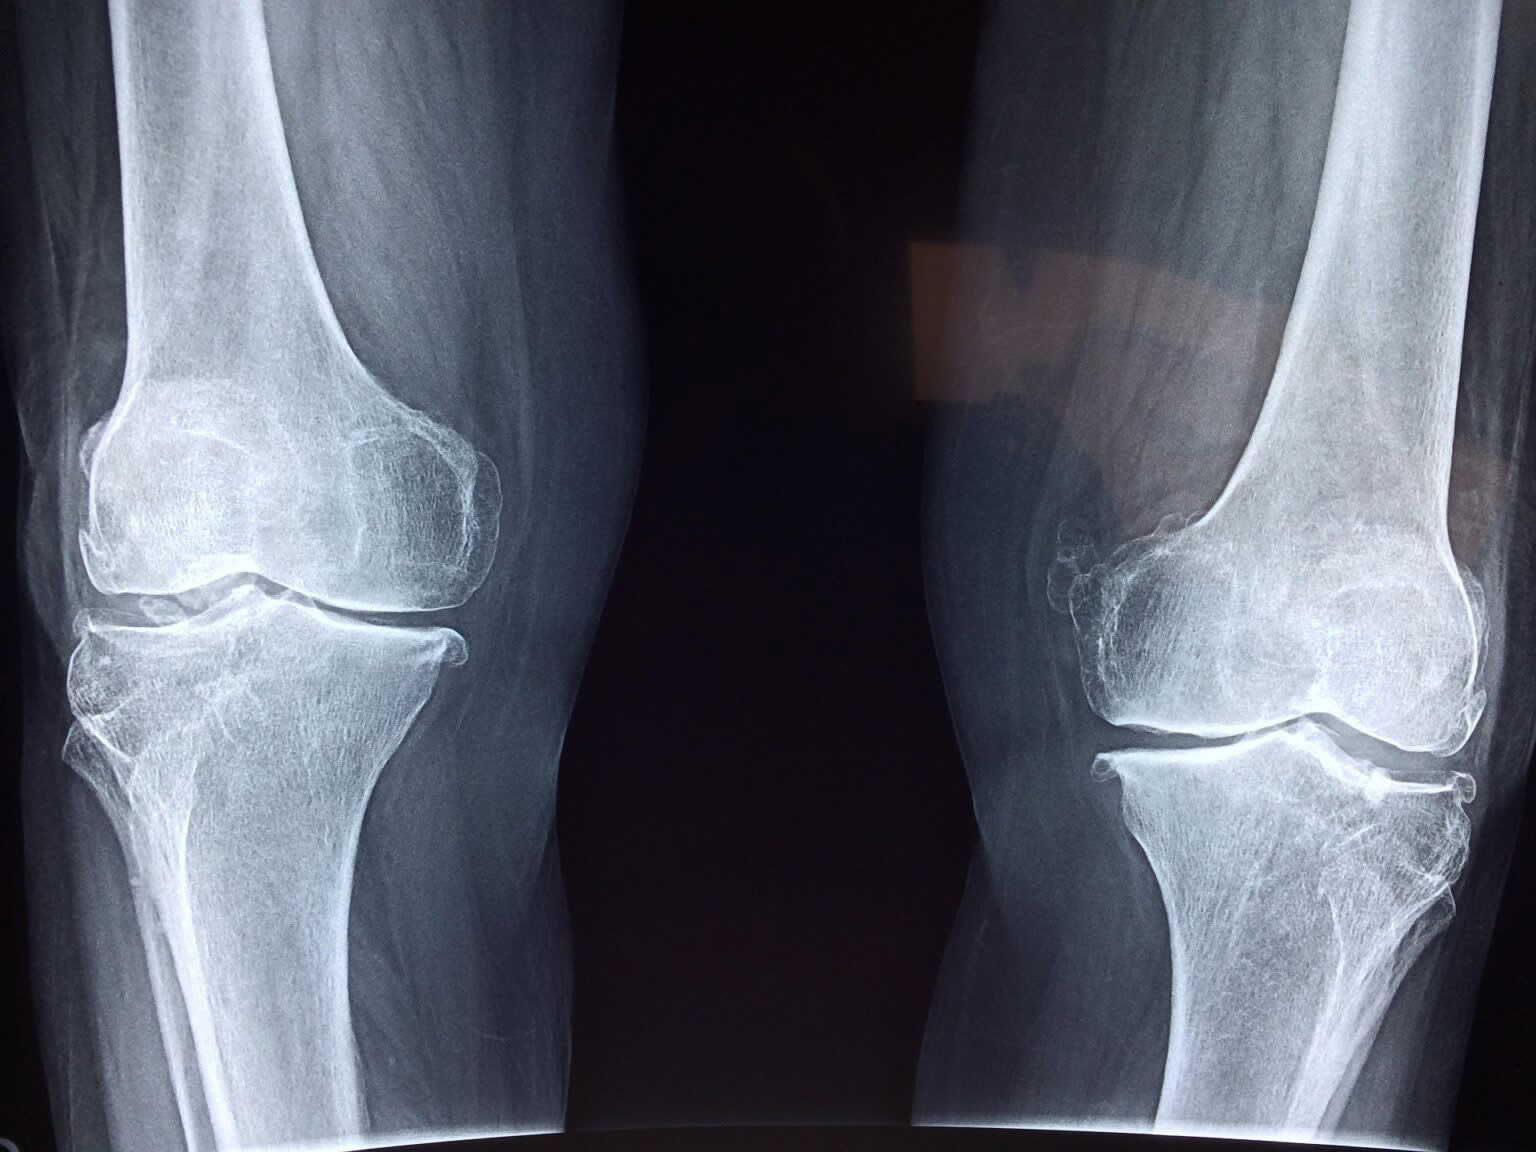

With an aging population, sport injuries and obesity among the causes, the rate of joint replacement surgery is increasing at a rapid rate. Currently more than 85,000 hip and knee replacements are undertaken each year in Australia. The outcomes of joint replacement are variable.